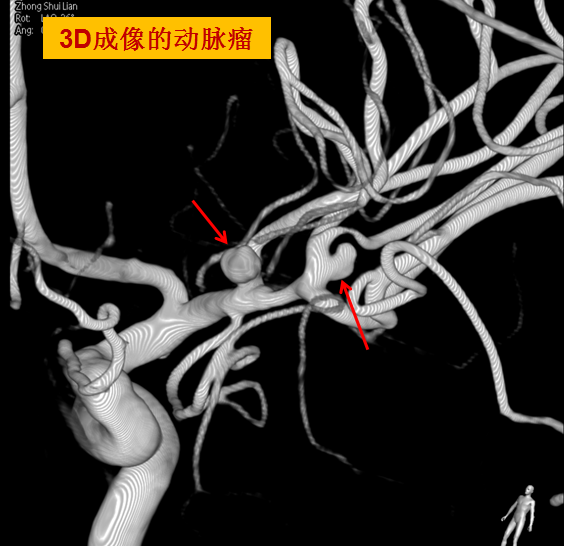

此患者自发性蛛网膜下腔出血、脑内出血最大可能的原因就是颅内的血管病变--颅内动脉瘤破裂,须立刻完善脑血管造影检查(DSA)进一步查明出血原因,取得钟阿姨家属同意后,便开通绿色手术通道进行介入手术。